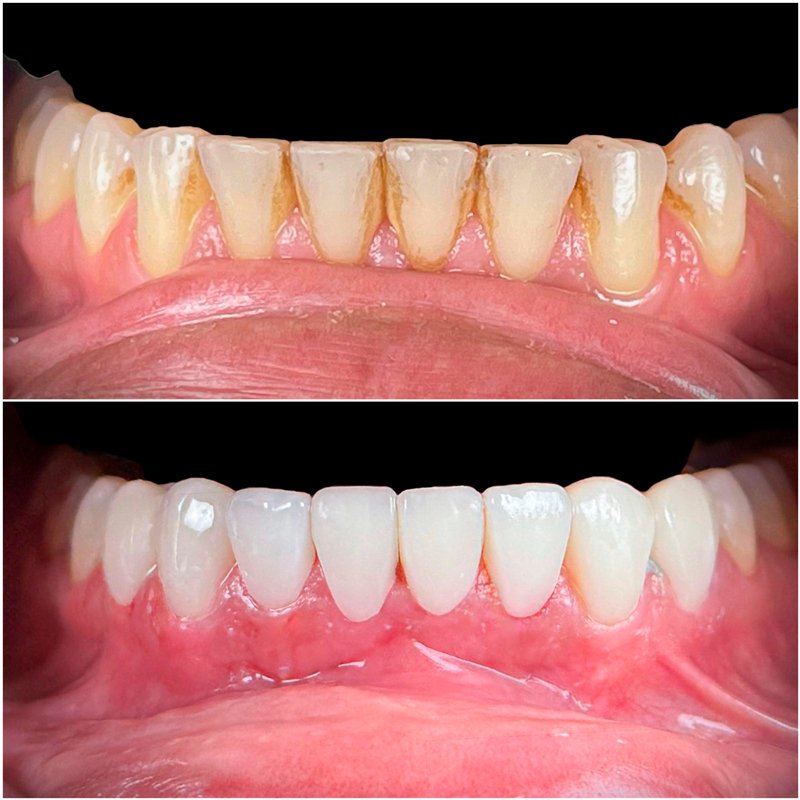

Creí, durante muchos años, que nunca iba a volver a verme sonreir en el espejo. Perdí todos mis dientes. Cuando tomaban fotos evitaba reirme. Perdí la seguridad para hablar en público, incluso comer fuera de casa mi casa me daba vergüenza.

Decidí recuperar mi sonrisa y fui a la clínica dental donde me atendió la Dra. Laura Zárate. Me explico paso a paso como sería el procedimiento. Resolvió todas mis dudas y me dio la confianza para iniciar el tratamiento.

Hoy, gracias a mi prótesis híbrida, puedo reír, comer y hablar con total naturalidad. Recuperé mi sonrisa, mi confianza, mi alegría. Hoy puedo decir que recupere mi calidad de vida